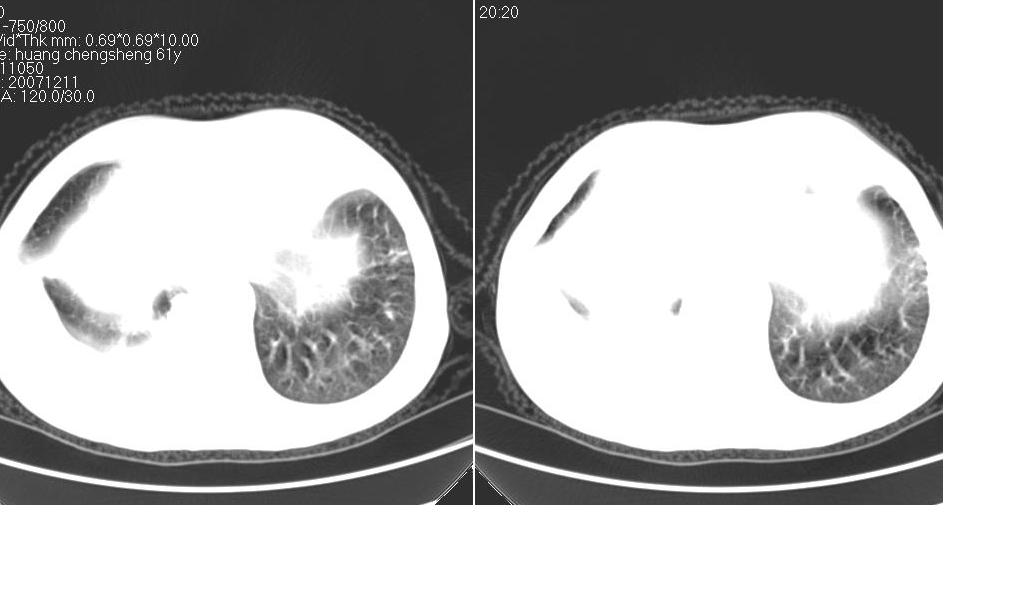

标题: CT10843:男 61岁,胸部CT平扫 [打印本页]

标题: CT10843:男 61岁,胸部CT平扫

男 61岁,已确诊肺癌半年余.

右肺小细胞肺癌并纵隔淋巴结转移。胸腔积液,心包少量积液。左肺改变不除外癌性淋巴管炎

考虑:1、右肺下叶中心型肺癌并纵隔淋巴结转移。胸腔积液。

2、心包少量积液。

3、左肺改变不除外癌性淋巴管炎或化疗后肺间质纤维化。

1 右肺下叶中心型肺癌.纵隔内淋巴结转移.右侧胸腔积液. 2 心包少量积液.3 肺间性改变考虑与化疗有关.